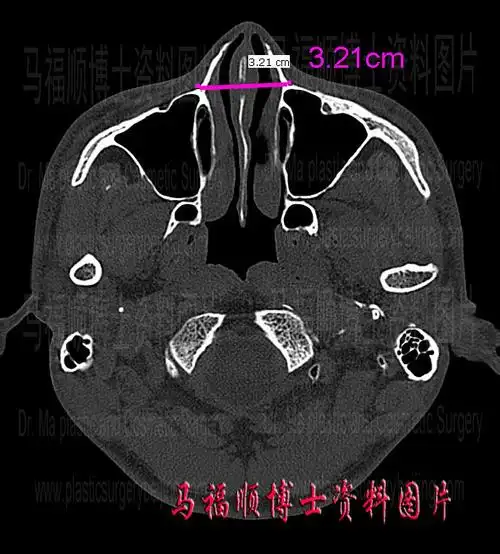

总而言之,鼻骨宽的表现为:从视觉上感觉鼻